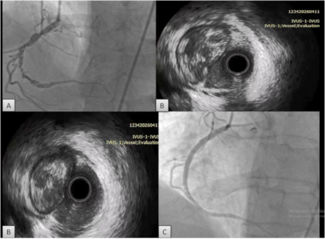

Two 8 French (Fr) sheaths (Cordis Corporation, Warren, New Jersey) were  placed in the right femoral vein. A right atrial angiogram was performed with a 6 Fr pigtail catheter (Cordis Corporation) (Figure 3). An 8 Fr Acuson AcuNav intracardiac echo probe (Siemens Medical USA, Malvern, Pennsylvania) was inserted into the right atrium. This was used to visualize the mass (Figure 4). A Mullins sheath (Medtronic, Inc., Minneapolis, Minnesota) was used to guide biopsy forceps (Argon Medical, Athens, Texas) to obtain specimens from the right atrial mass (Figure 5).

placed in the right femoral vein. A right atrial angiogram was performed with a 6 Fr pigtail catheter (Cordis Corporation) (Figure 3). An 8 Fr Acuson AcuNav intracardiac echo probe (Siemens Medical USA, Malvern, Pennsylvania) was inserted into the right atrium. This was used to visualize the mass (Figure 4). A Mullins sheath (Medtronic, Inc., Minneapolis, Minnesota) was used to guide biopsy forceps (Argon Medical, Athens, Texas) to obtain specimens from the right atrial mass (Figure 5).

Discussion. There are previous reports in the literature of using ICE to guide intracardiac biopsy procedures. One report utilized the right femoral vein for the ICE catheter and the right subclavian vein for specimen harvesting.6 Another report used a fixed needle system via the right internal jugular and right femoral veins.7 The approach chosen in our case was the most familiar and least complex via the right femoral vein. The Mullins sheath provided directional control and delivery of the biopsy forceps from this access point. The ICE catheter ensured the proper location of the sheath/forceps system in relation to the mass. In previous cases, there has been difficulty using fluoroscopy or even transesophageal echo guidance to direct a bioptome inside the cardiac chambers to retrieve catheter pieces or to obtain a biopsy specimen. With the use of ICE, the probe can be placed next to the tissue and visualize the tip of the bioptome as it touches the echogenic structure to be biopsied. To accomplish this, it is necessary to initially image the mass with the ICE catheter close to the mass. Then using fluoroscopy, bring the bioptome up to the ICE catheter tip. The bioptome tip can then be seen on the ICE image as it touches and moves the mass.